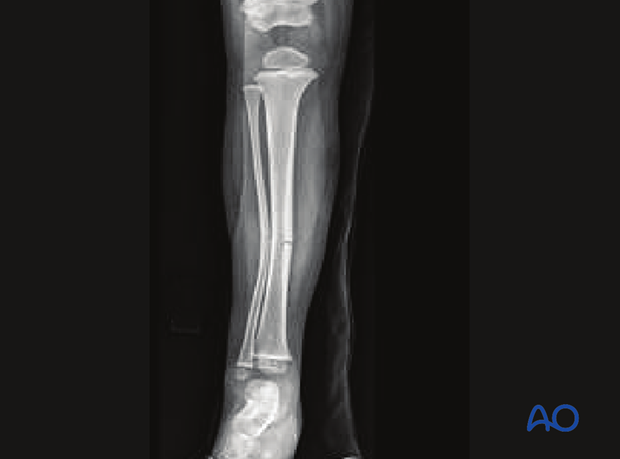

What are the steps in the repair of a fracture?

hematoma formation

fibrocartilaginous

bony (hard) callus formation

bone remodeling

Fractures

are breaks or cracks in bones.

greenstick

Impacted

Closed

Open

Comminuted

Pott’s

Colles’

Stress